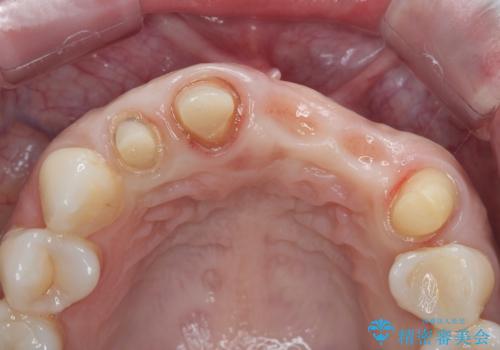

- 前歯がグラグラし、においもする、とのことで改善を求めて来院されました。

一見して問題ないように見える左側の2前歯は、セラミックを除去してみると亀裂や虫歯の再発が見られました。

抜歯時に可及的に歯肉のボリュームを保つよう骨充填材とコラーゲン製剤による填塞を行い審美的かつ機能的なブリッジとなるよう治療を進めます。